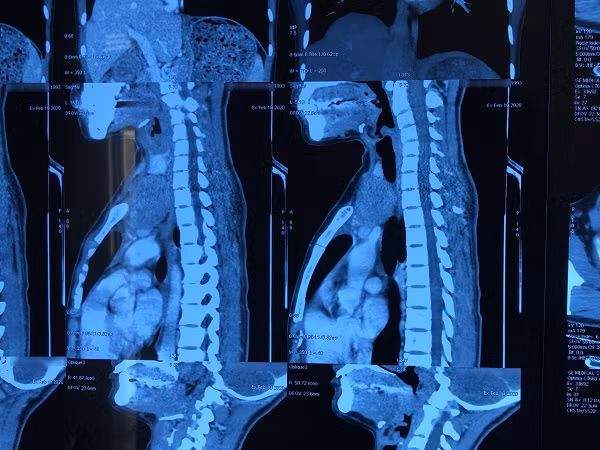

Hình ảnh phim chụp khối u tuyến ức lạc chỗ ở cổ (Ảnh: BSCC)

Thời điểm nhập viện, khối u có kích thước tương đối lớn khiến cổ bệnh nhân bị sưng lệch hẳn sang bên trái. Qua thăm khám, bệnh nhân được chẩn đoán u tuyến ức type AB tại vị trí trung thất trước trên và một phần vùng cổ trái kích thước 8x5cm, hay còn gọi là u tuyến ức lạc chỗ.